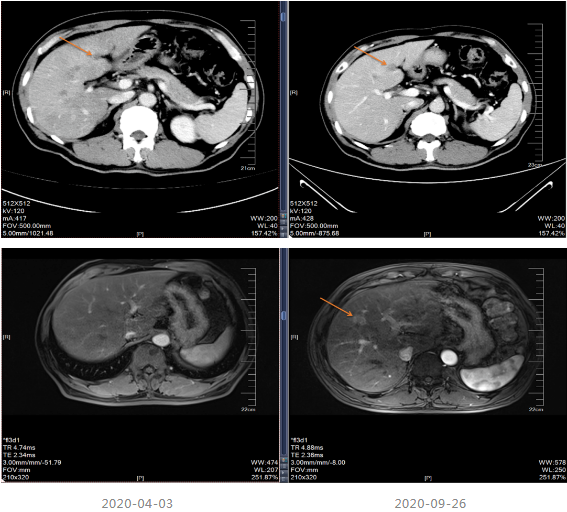

治疗期间于2019-07-13及2019-12-19进行疗效评估,疗效评价PR,建议患者切除原发灶,患者拒绝。CEA、CA199降至正常范围。

局部治疗:2020-09-26复查MRI提示部分病灶较前缩小,部分增大,于2020-10-22至武汉同济医院行“肝脏病灶微波消融术”,后继续口服卡培他滨至2021-5。